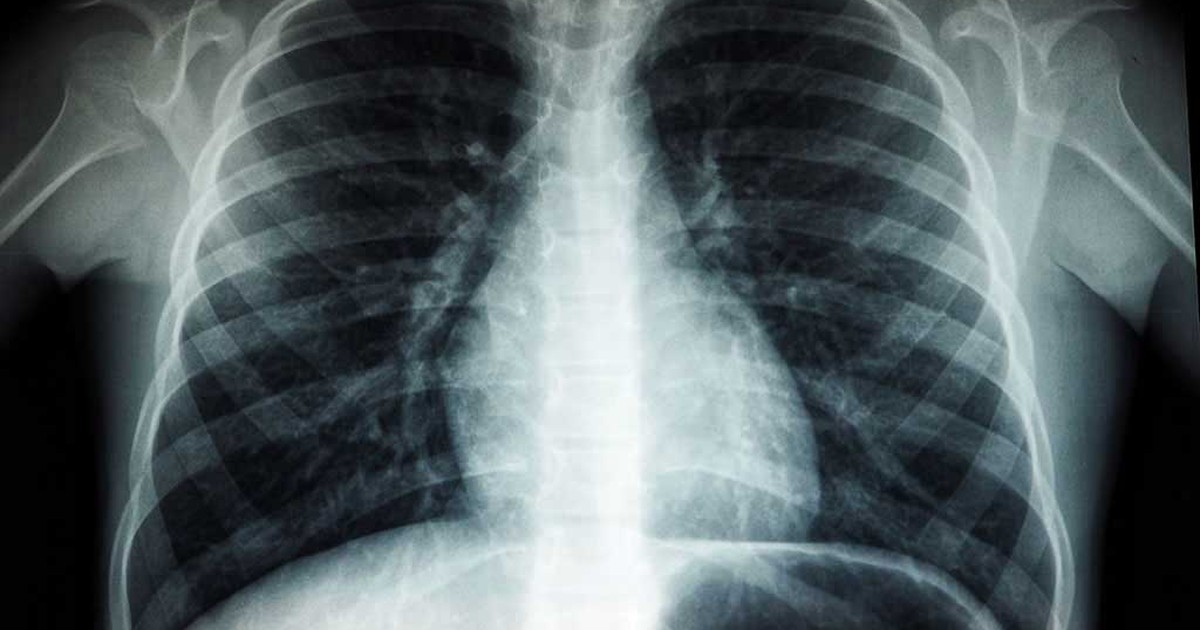

Theo một nghiên cứu mới được công bố trên tạp chí Radiology , phim chụp CT phổi của bệnh nhân “viêm phổi” do Covid-19 cho thấy phổi của họ vẫn bị tổn thương kéo dài cả năm kể từ khi bắt đầu xuất hiện các triệu chứng, theo tạp chí y khoa News Medica l (Anh).